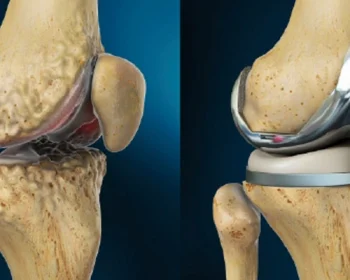

Complex knee replacement is an advanced surgical procedure for severe knee damage, often involving customized implants to restore stability, alignment, and function.

Unicondylar knee replacement, or partial knee replacement, targets only the damaged knee compartment, preserving healthy tissue for a quicker recovery and natural movement.